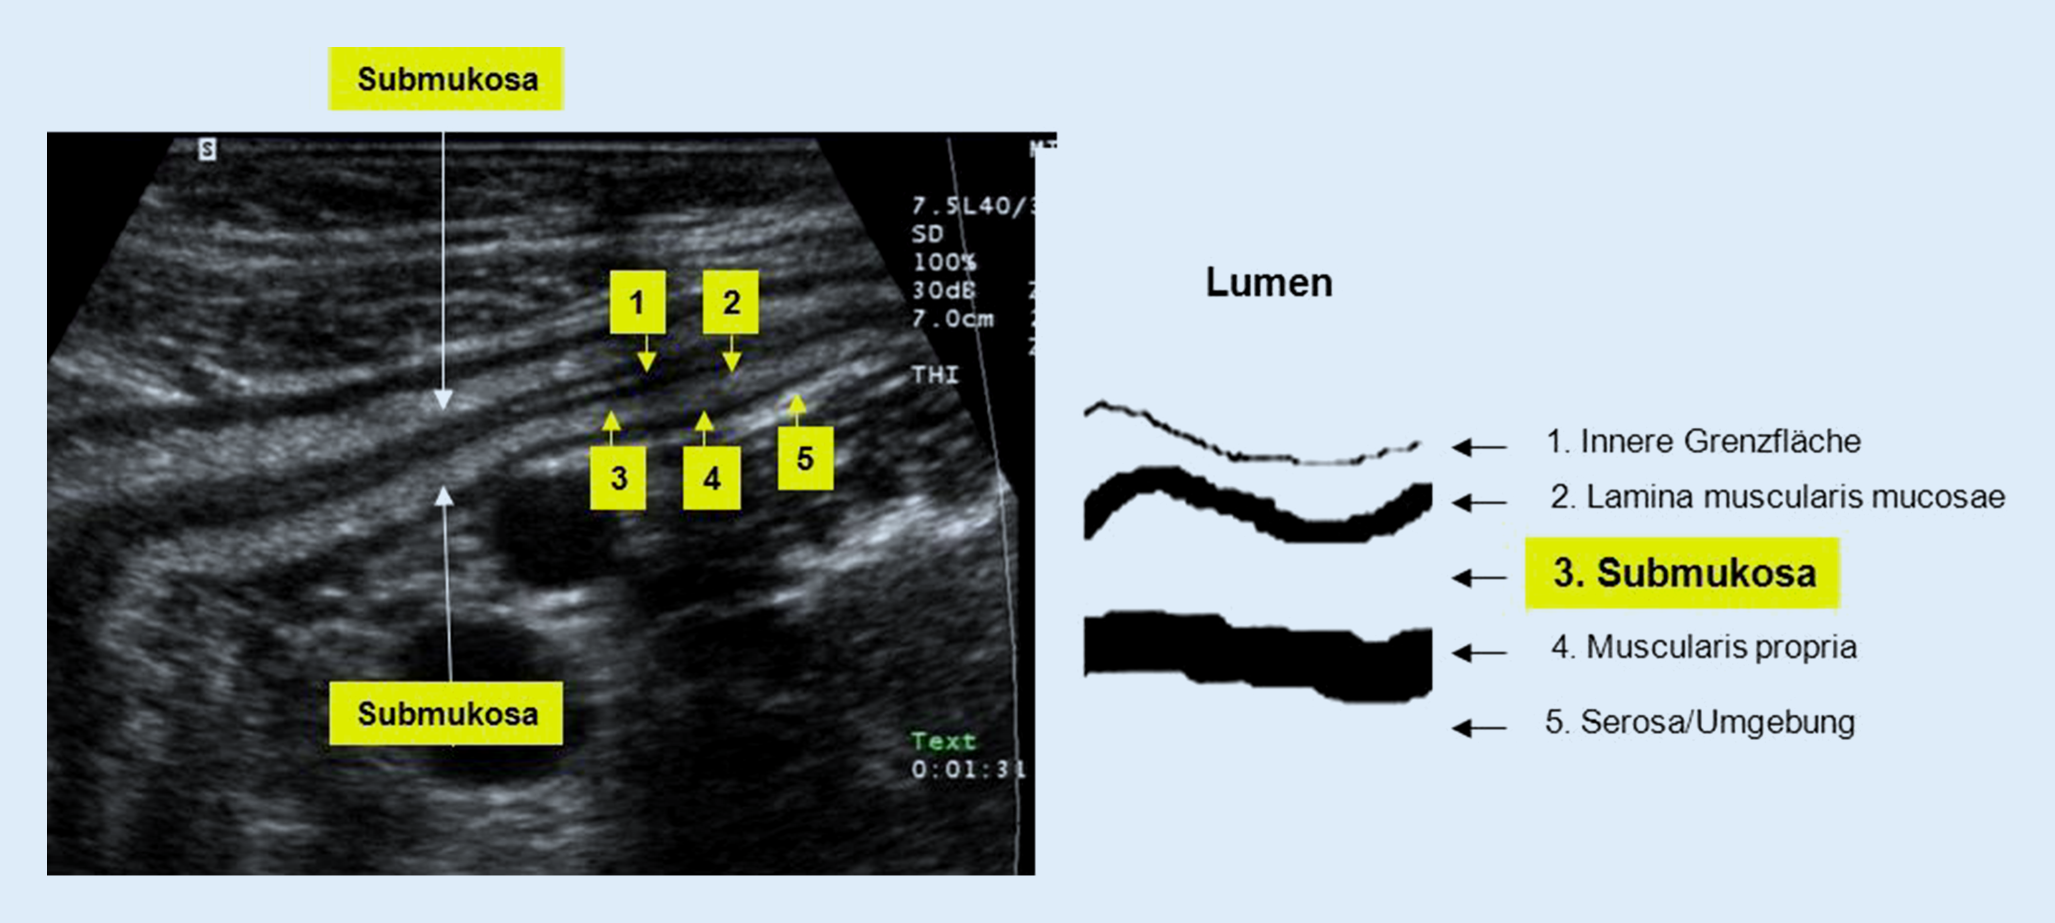

Neben der Messung der Darmwanddicke und der Erfassung der Vaskularisation sollten beim Ultraschall des Darms weitere Parameter erfasst werden [4]. Hierzu gehört als Erstes der Erhalt der Stratifizierung der Darmwand. Diese ist in Abb. 1 dargestellt. Bei der Colitis ulcerosa oder bei infektiösen Gastroenteritiden bleibt diese Stratifizierung der Darmwand erhalten, auch wenn die Darmwanddicke zunimmt. Beim Morbus Crohn oder bei der intestinalen Tuberkulose wird die Stratifizierung regional aufgelöst. Im Allgemeinen wird dies auf das Entzündungszell-Infiltrat zurückgeführt. Liegt eine Veränderung der Darmwand vor, kann die Länge dieser Alteration abgeschätzt werden. Eine zuverlässige Ausmessung der Länge des Befalls ist nicht immer einfach, da durch die dreidimensionale Struktur der Bauchhöhle bei längerstreckigem Befall eines Morbus Crohn die gesamte Länge der Veränderung selten in einem Ultraschallschnitt dargestellt werden kann. Dies wäre nur mit dreidimensionalen Rekonstruktionen möglich, was aber auch für die Schnittbildgebung gilt.

Abb. 1

Schichten der Darmwand im Darmultraschall. (Bei in diesem Fall deutlich pathologischer Verbreiterung der Submukosa, die sonst nur als dünnes echoreiches Band sichtbar ist)